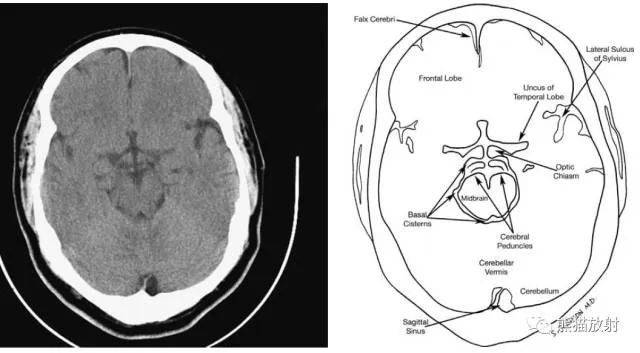

从前至后:大脑镰、额叶、侧脑室前角、尾状核头、基底节正常钙化、内囊、基底节、三脑室、颞叶、中脑导水管、环池、小脑蚓、枕叶。

从前至后:大脑镰、透明隔、尾状核、丘脑、侧脑室三角区脉络丛正常钙化、大脑镰。

从前至后:大脑镰、额叶、灰白质交界处、侧脑室、大脑镰、枕叶、矢状窦。

从前至后:大脑镰、放射冠。